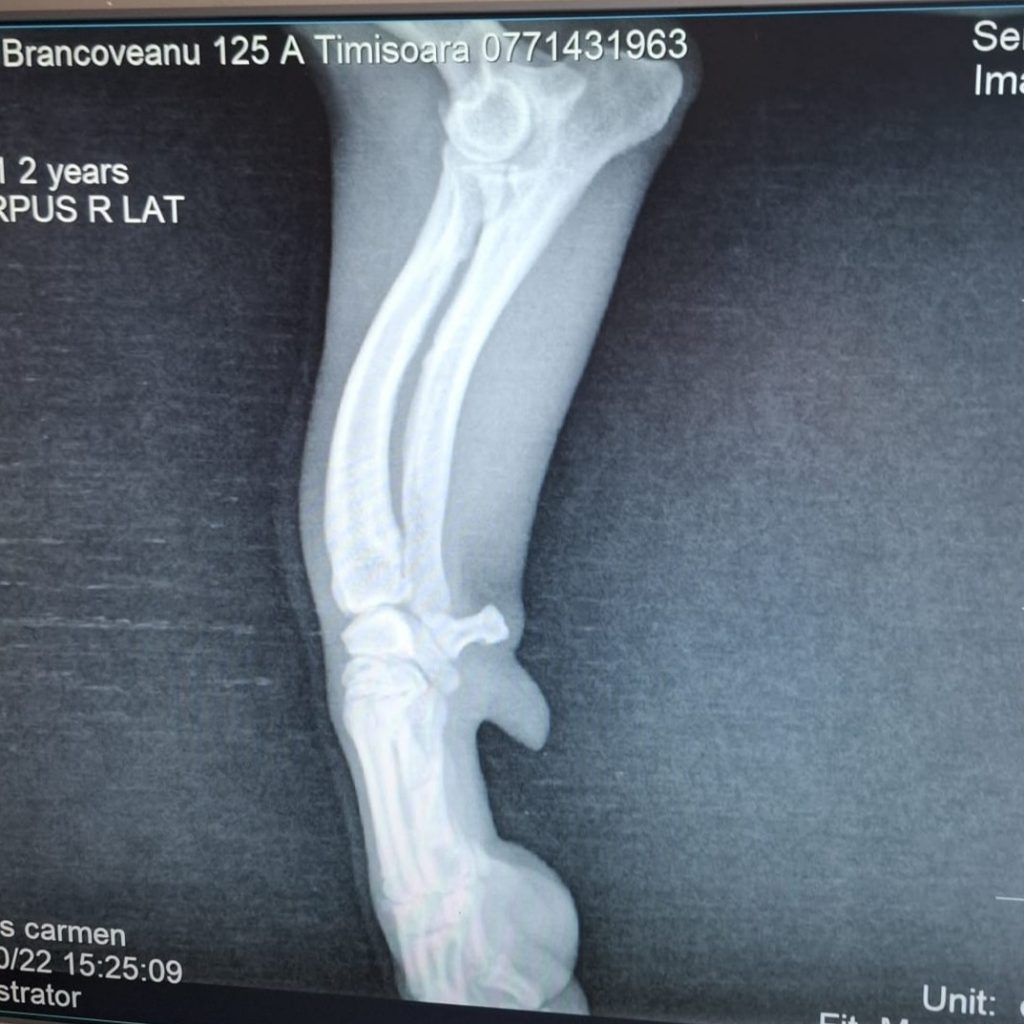

Licas ist ca. 11/24 geboren, etwa 30 cm groß und wiegt ungefähr 7 kg. Er wurde gemeinsam mit seiner Mama verlassen auf einem Feld in Rumänien gefunden. Eine Tierschützerin hat die zwei aufgenommen – das war bereits im Oktober letzten Jahres. Doch Licas brachte ein schweres Schicksal mit: Sein Vorderbein ist gelähmt. Nach dem Röntgen stand fest – eine Amputation oder eine Prothese könnten ihm helfen, schmerzfrei und unbeschwert durchs Leben zu gehen.